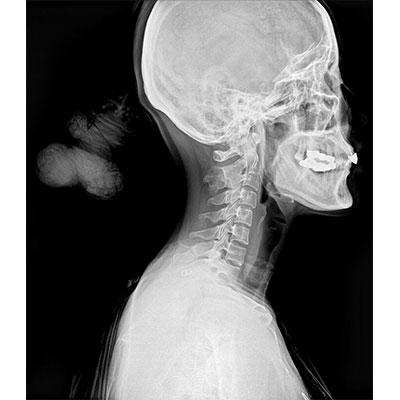

● 采用自主研發的技術,在保證優質圖像的前提下,大大降低X射線劑量,用心呵護醫護工作者及患者的健康。

● 短曝光時間,便于老年人、兒童、殘疾人進行臨床拍攝。避免這類群體因不能有效控制身體運動等因素造成的運動偽影,提高攝片質量及效率。